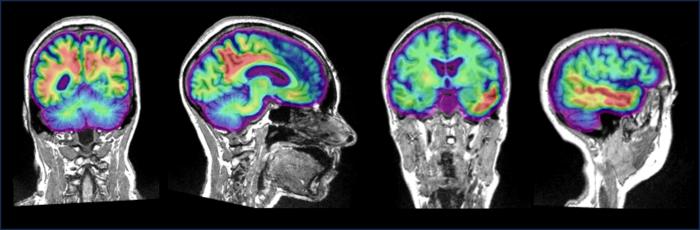

The team led by Jonathan Gallego Rudolf, a Ph.D. candidate in Baillet and Villeneuve’s labs, recruited 104 people with a family history of Alzheimer’s. They scanned the participants’ brains using a combination of positron emission tomography (PET) to detect the presence and location of the proteins and magnetoencephalography (MEG) to record brain activity in these regions.

The scientists compared the results of the two scans and found that brain areas with increased levels of amyloid-beta showed macroscopic expressions of brain hyperactivity, reflected by increased fast- and decreased slow-frequency brain activity. For people with both amyloid-beta and tau in their brain, the pattern shifted towards hypoactivity, with higher levels of pathology leading to brain activity slowing.